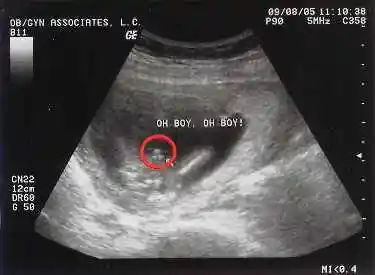

就可以了不过,建议最好是怀孕12-13周的时候再测,有90%以上的准确率

孕囊大小38*23mm,男宝宝7周1天,孕囊大小:29*19mm,男孩5周6天,孕囊